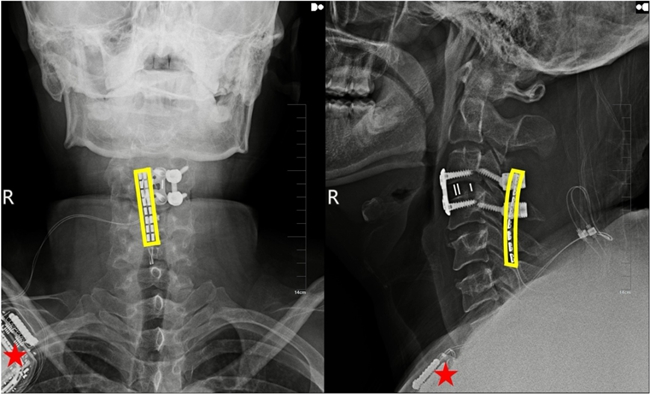

植入術后X線顯示,黃色方框為電極位置,星號為皮下脈沖發射器位置。